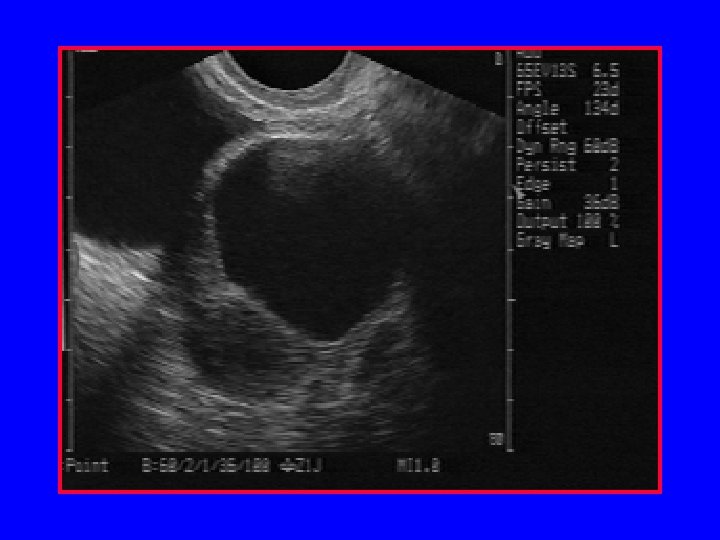

Empty gestational sac

Fetal demise